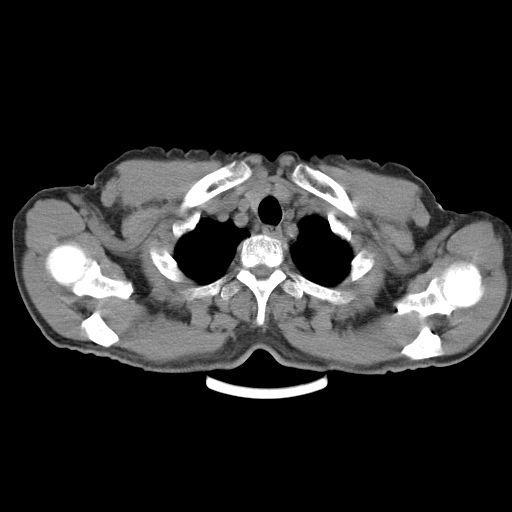

以下是引用心路寻觅在2010-3-1 10:23:00的发言:[br]1、考虑左肺上叶周围型肺癌[br]2、右上肺陈旧性病灶。[br][br][本贴已被 心路寻觅 于 2010-3-1 10:40:18 修改过]

以下是引用shuiyuan在2010-3-1 10:45:00的发言:[br]考虑左肺上叶中心型肺癌伴阻塞型炎症,邻近胸膜受侵。